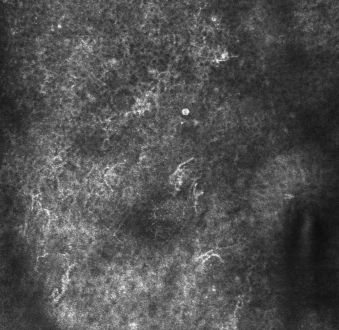

反射式共聚焦显微镜下活动期黄褐斑见较多高折光、树突状细胞